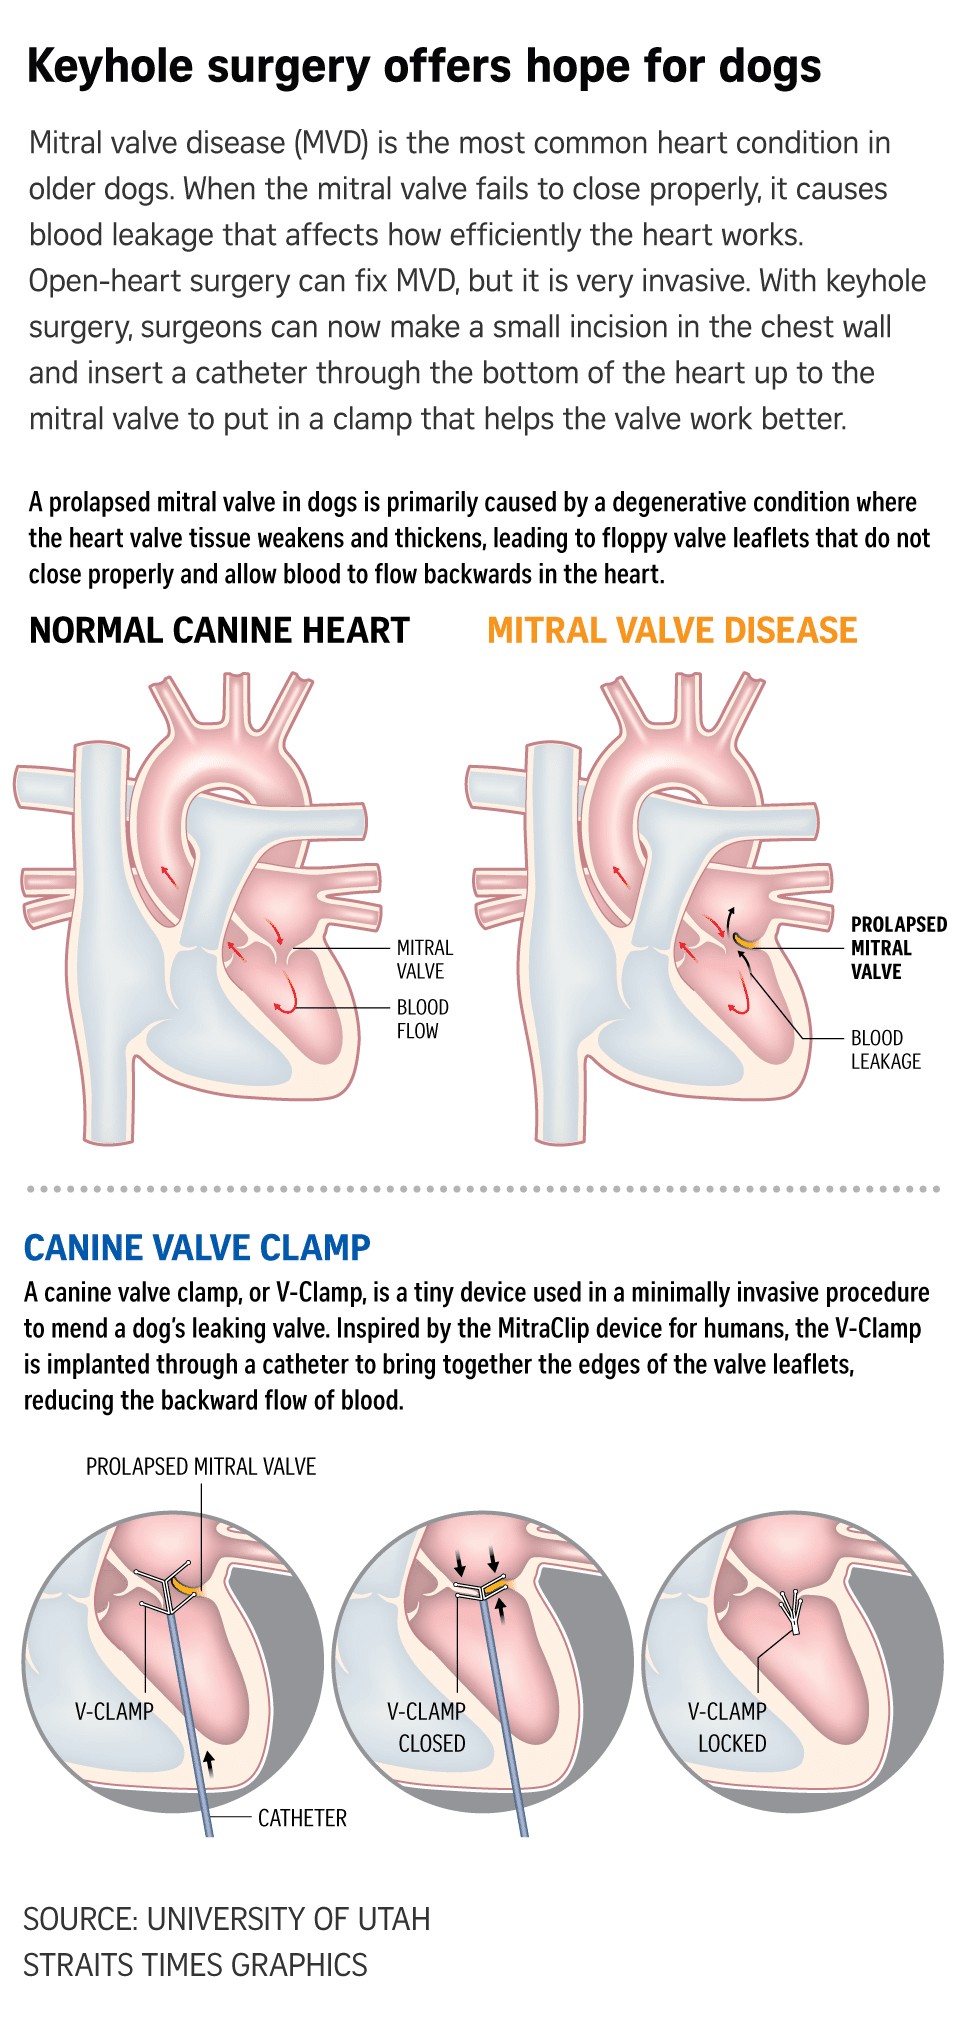

“Instead of open-heart surgery, I make a small opening from the side of the chest and introduce a V-Clamp device (canine valve clamp) through a catheter into the dog’s beating heart, guided by video X-rays and a 3D heart scan,” Dr Chow, 36, explained.

Inspired by the MitraClip device for humans, the V-Clamp – approximately 8mm in length – clips the leaky mitral valve leaflets together, reducing the backflow of blood into the heart chambers and improving its function.

It also slows down congestive heart failure, and scientific literature said it reduces the severity of the mitral valve leak by between 50 per cent and 90 per cent.

The procedure is carried out while the heart is still beating – a marked difference from the traditional open-heart surgery, where the veterinary surgeon needs to cut through the breastbone to expose the heart and a heart-lung bypass machine is used as the animal’s heart is stopped.